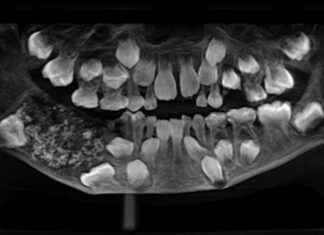

Cirurgia em menino de 7 anos remove 526 dentes em massa rara

O que começou como um simples inchaço no maxilar de um menino de 7 anos em Chennai, na Índia, acabou se tornando um dos...